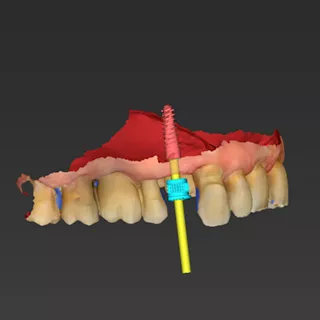

• Phase III: Digital implant planning using coDiagnostiX® for guided placement of an Axiom Bone Level implant with Healfit® SH healing abutment and simultaneous connective tissue grafting to enhance peri-implant stability (Fig 2 a&b, 3 a-c).

2a. 2b. Implant and Healfit® SH planning in coDiagnostiX®.

3a. 3b. 3c CAD design of the tooth-supported surgical guide in coDiagnostiX®. Superimposition of the guide on the 3D bone model for fit verification prior to fabrication.

Phase III: Guide design (Fig 3a. 3b. 3c) for guided Implant Placement and Soft-Tissue Augmentation

After healing, implant placement was performed using a tooth-supported surgical guide under local anaesthesia. A limited buccal flap allowed visual control and creation of a pouch for a connective tissue graft. Osteotomy was completed with the Integral surgery kit, and a 3.4×12 mm Axiom® X3 implant (XT34120) was placed under fully guided conditions with a Healfit® SH (OPSHSC23) healing abutment connected. A palatal connective tissue graft was positioned buccally to enhance soft-tissue thickness. The flap was sutured with 5-0 interrupted and mattress sutures. Postoperative care mirrored Phase I, with uneventful healing observed (Fig 4 a&b).